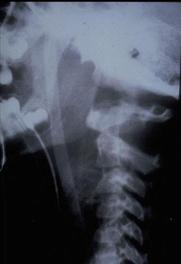

TRAUMA CERVICALA

Incidenta laterala Incidenta

laterala Incidenta

antero-posterioara

Aspect normal Imagine

incompleta Aspect

normal